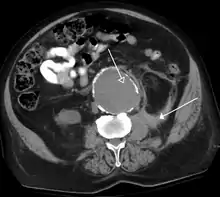

An axial contrast-enhanced CT scan demonstrating an abdominal aortic aneurysm of 4.8 by 3.8 cm